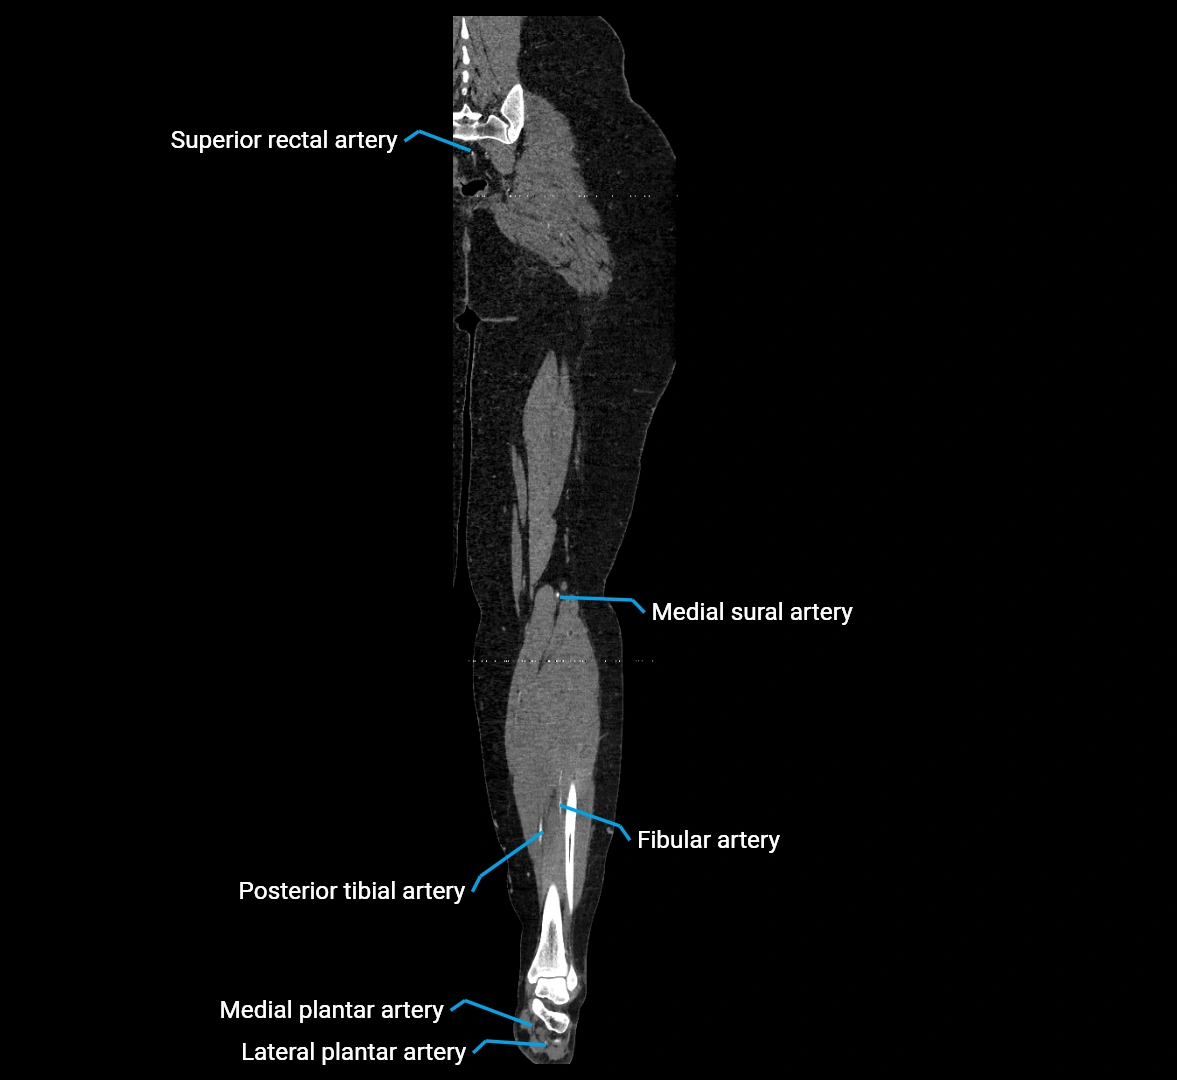

CT images

image